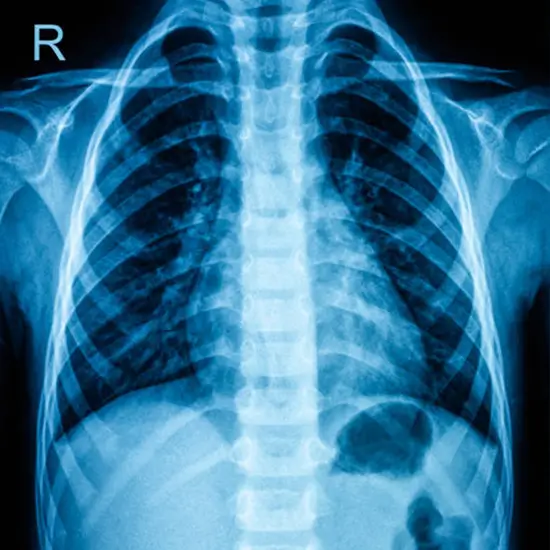

Screening the chest is a way to examine the chest area with imaging. It helps find anything wrong with the area's thorax, rib cage, lungs, heart, spinal cord, or other tissues and muscles.

This test is suggested to find out what is causing a persistent fever, cough, or any strange things that appear on a plain x-ray.

It may also help doctors figure out what's wrong with people with bronchitis, pneumonia, tuberculosis, or chest tumours.

MRI (Magnetic Resonance Imaging) screening of the Chest is a non-invasive radiology test used to evaluate the condition of the Chest and surrounding tissue. MRI Screening Of Chest is done to look for Chest conditions and the surrounding area.